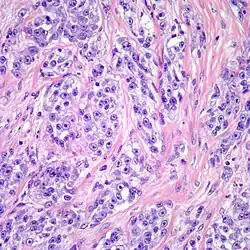

| Clear cell sarcoma. Tumor cells with prominent nucleoli and clear cytoplasm are arranged in well-defined nests surrounded by dense fibrous stroma. | |

Despite the name clear cell sarcoma, the tumor cells do not necessarily need to have clear cytoplasm. The lesion has a distinctly nested growth pattern with a mixture of spindle, epithelioid and tumor giant cells. Approximately two thirds of the tumors contain melanin pigment. Clear cell sarcoma, similar to melanoma, has consistent positivity for S-100, HMB-45, and MITF.[6]